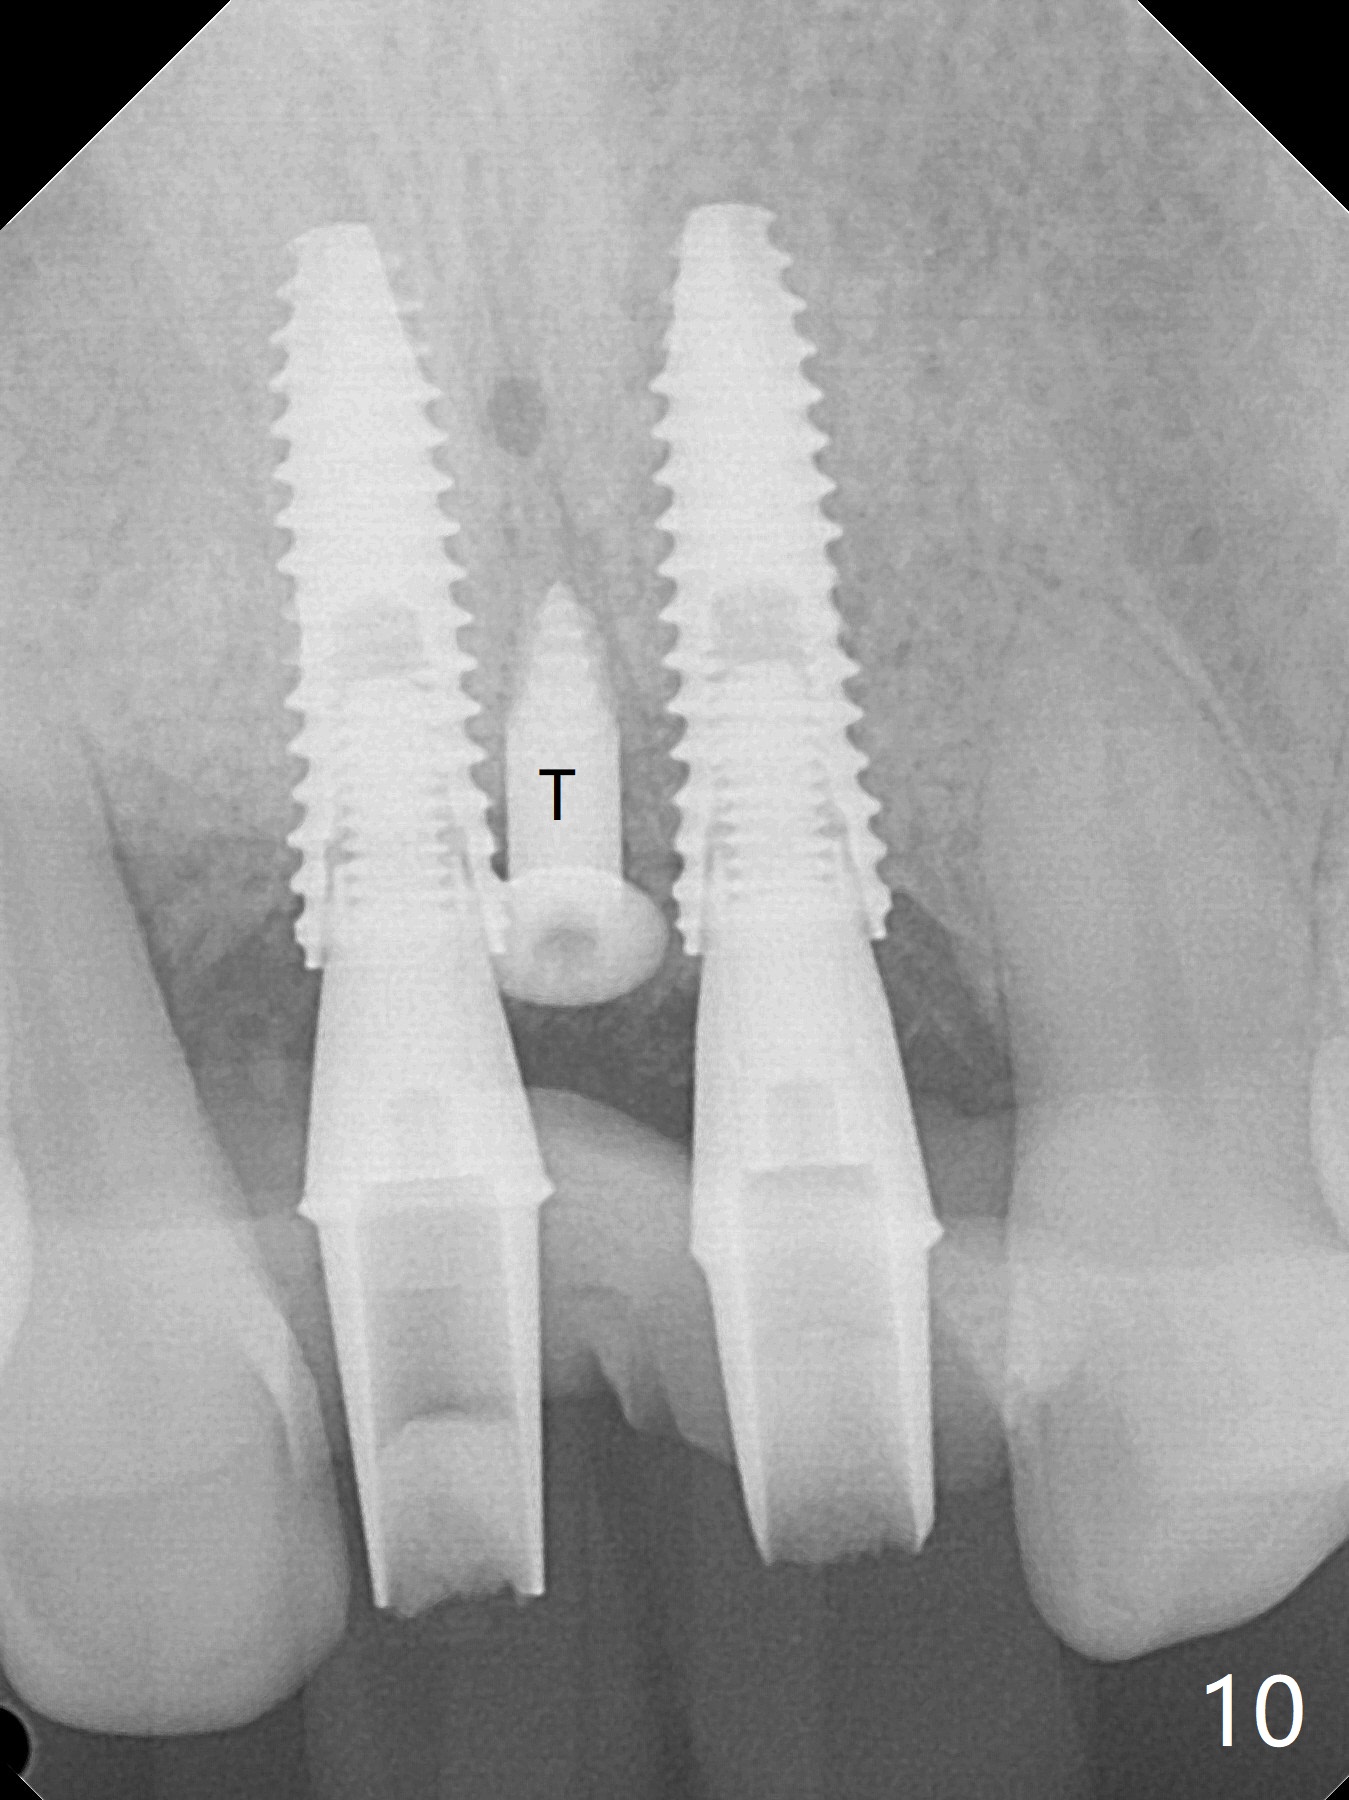

The gingiva remains recessive at #8 and 9 six months post immediate implant placement with bone graft (Fig.1). The buccal plate at #8 is particularly concave before (Fig.2 *) and after (Fig.3) abutment removal. The bony defect repair is assisted by placing a 4 mm tenting screw between the 2 implants (Fig.4) and placing allograft mixed with PRF (as putty) around the screw (Fig.5 (after replacement of the abutments)). The buccal contour improves because of the tenting screw and the bone graft placement (Fig.6 (as well as PRF and 6-month membranes)). The wound dehisces 12 days postop and immediately before leaving country for months (Fig.7). The sutures are removed, Osteogen plug is inserted (Fig.8) and periodontal dressing is applied (Fig.9). PA is taken to show the tenting screw (Fig.10 T). The latter is exposed 3 months postop (Fig.11,12). It appears that gingival graft is a must (Fig.13). Make a palatal stent, remove the temp with abutments and create a bleeding surface before harvesting a large piece of tissue. Connective tissue graft is done 5 months post bone graft (Fig.14). In fact there is no implant thread exposure. In fact the connective tissue graft does not survive. The abutments are re-prepared for pink porcelain (Fig.15). The bone loss is stable 1 year post cementation in spite of incomplete abutment seating (Fig.16). The soft tissue is nearly normal (Fig.17).